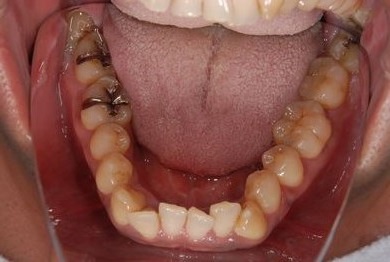

セラミック治療+歯肉歯槽骨整形術

| 性別/年齢 | 男性 / 45歳 | ||||||||||||||||||||||||||||||||

| 主訴 | 詰め物をしている歯が割れてしまったので、治療して欲しい。 | ||||||||||||||||||||||||||||||||

| 治療方針 | セラミック治療にて、審美的回復を行う。 | ||||||||||||||||||||||||||||||||

| 治療内容 | メタルボンドセラミッククラウン1本(メタルボンドセラミック用土台1本)、歯肉歯槽骨整形手術 | ||||||||||||||||||||||||||||||||

| 総治療費 | 157,185円 | ||||||||||||||||||||||||||||||||

| 治療期間 | 7ヶ月 |